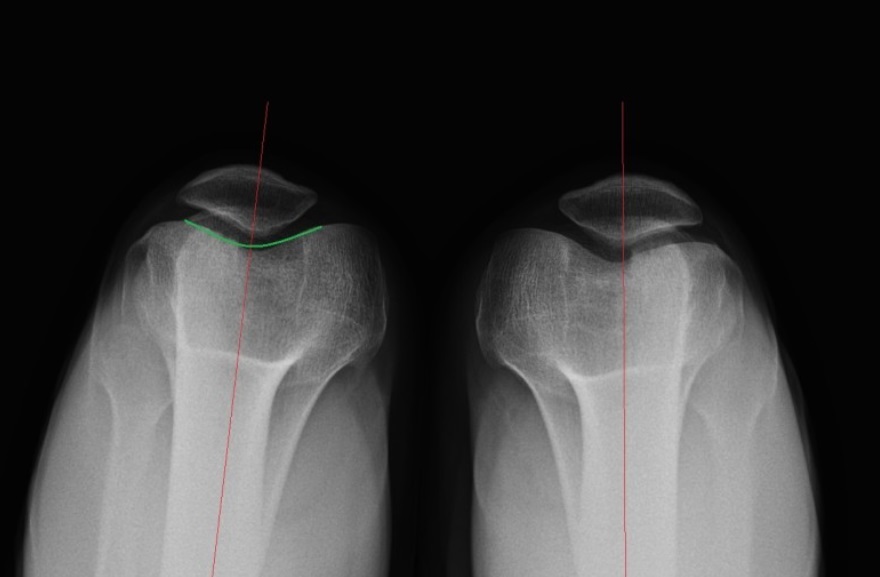

무릎통증 원인 검사방법

병원에 내원하여 무릎에 붓기가 있는지 무릎의 관절 각도가 얼마나 나오는지, 아픈 위치가 정확히 어딘지 확인해야합니다.

그리고 무릎의 연골판, 연골, 인대 등의 검사를 통해 뼈의 변형이나 관절의 휜 정도를 면밀하게 확인하여 진단해야합니다.